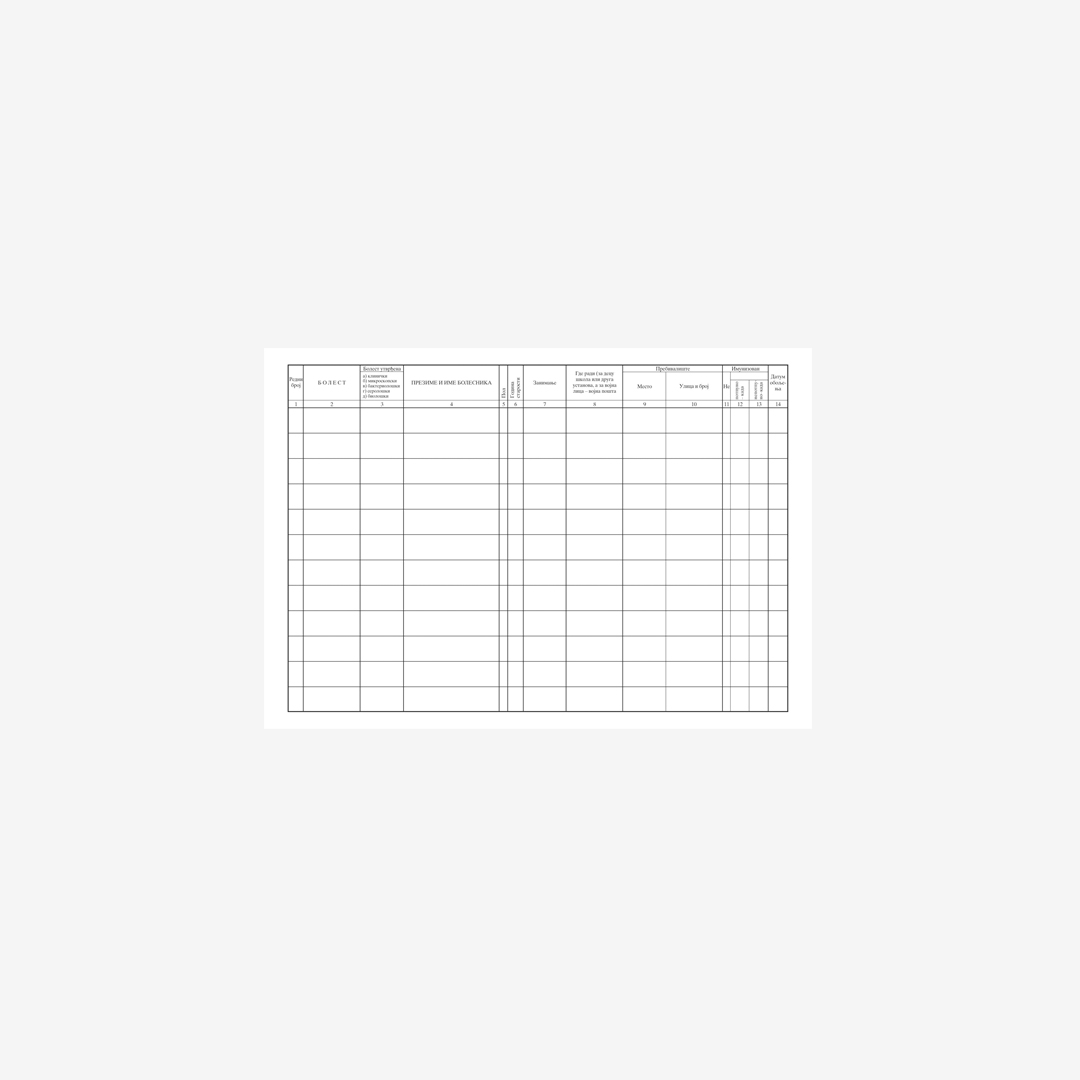

- Knjiga evidencija zaraznih bolesti tvrd povez, B4, 100 lista.